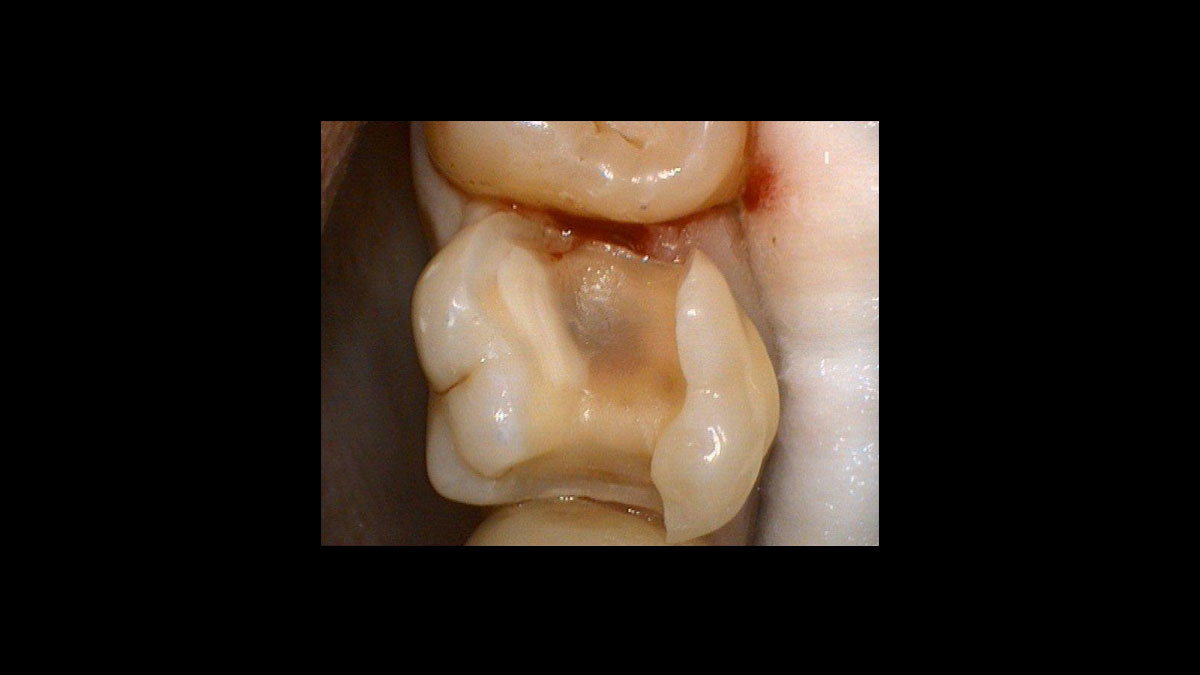

Preparación del tejido gingival antes de la toma de impresiones dentales